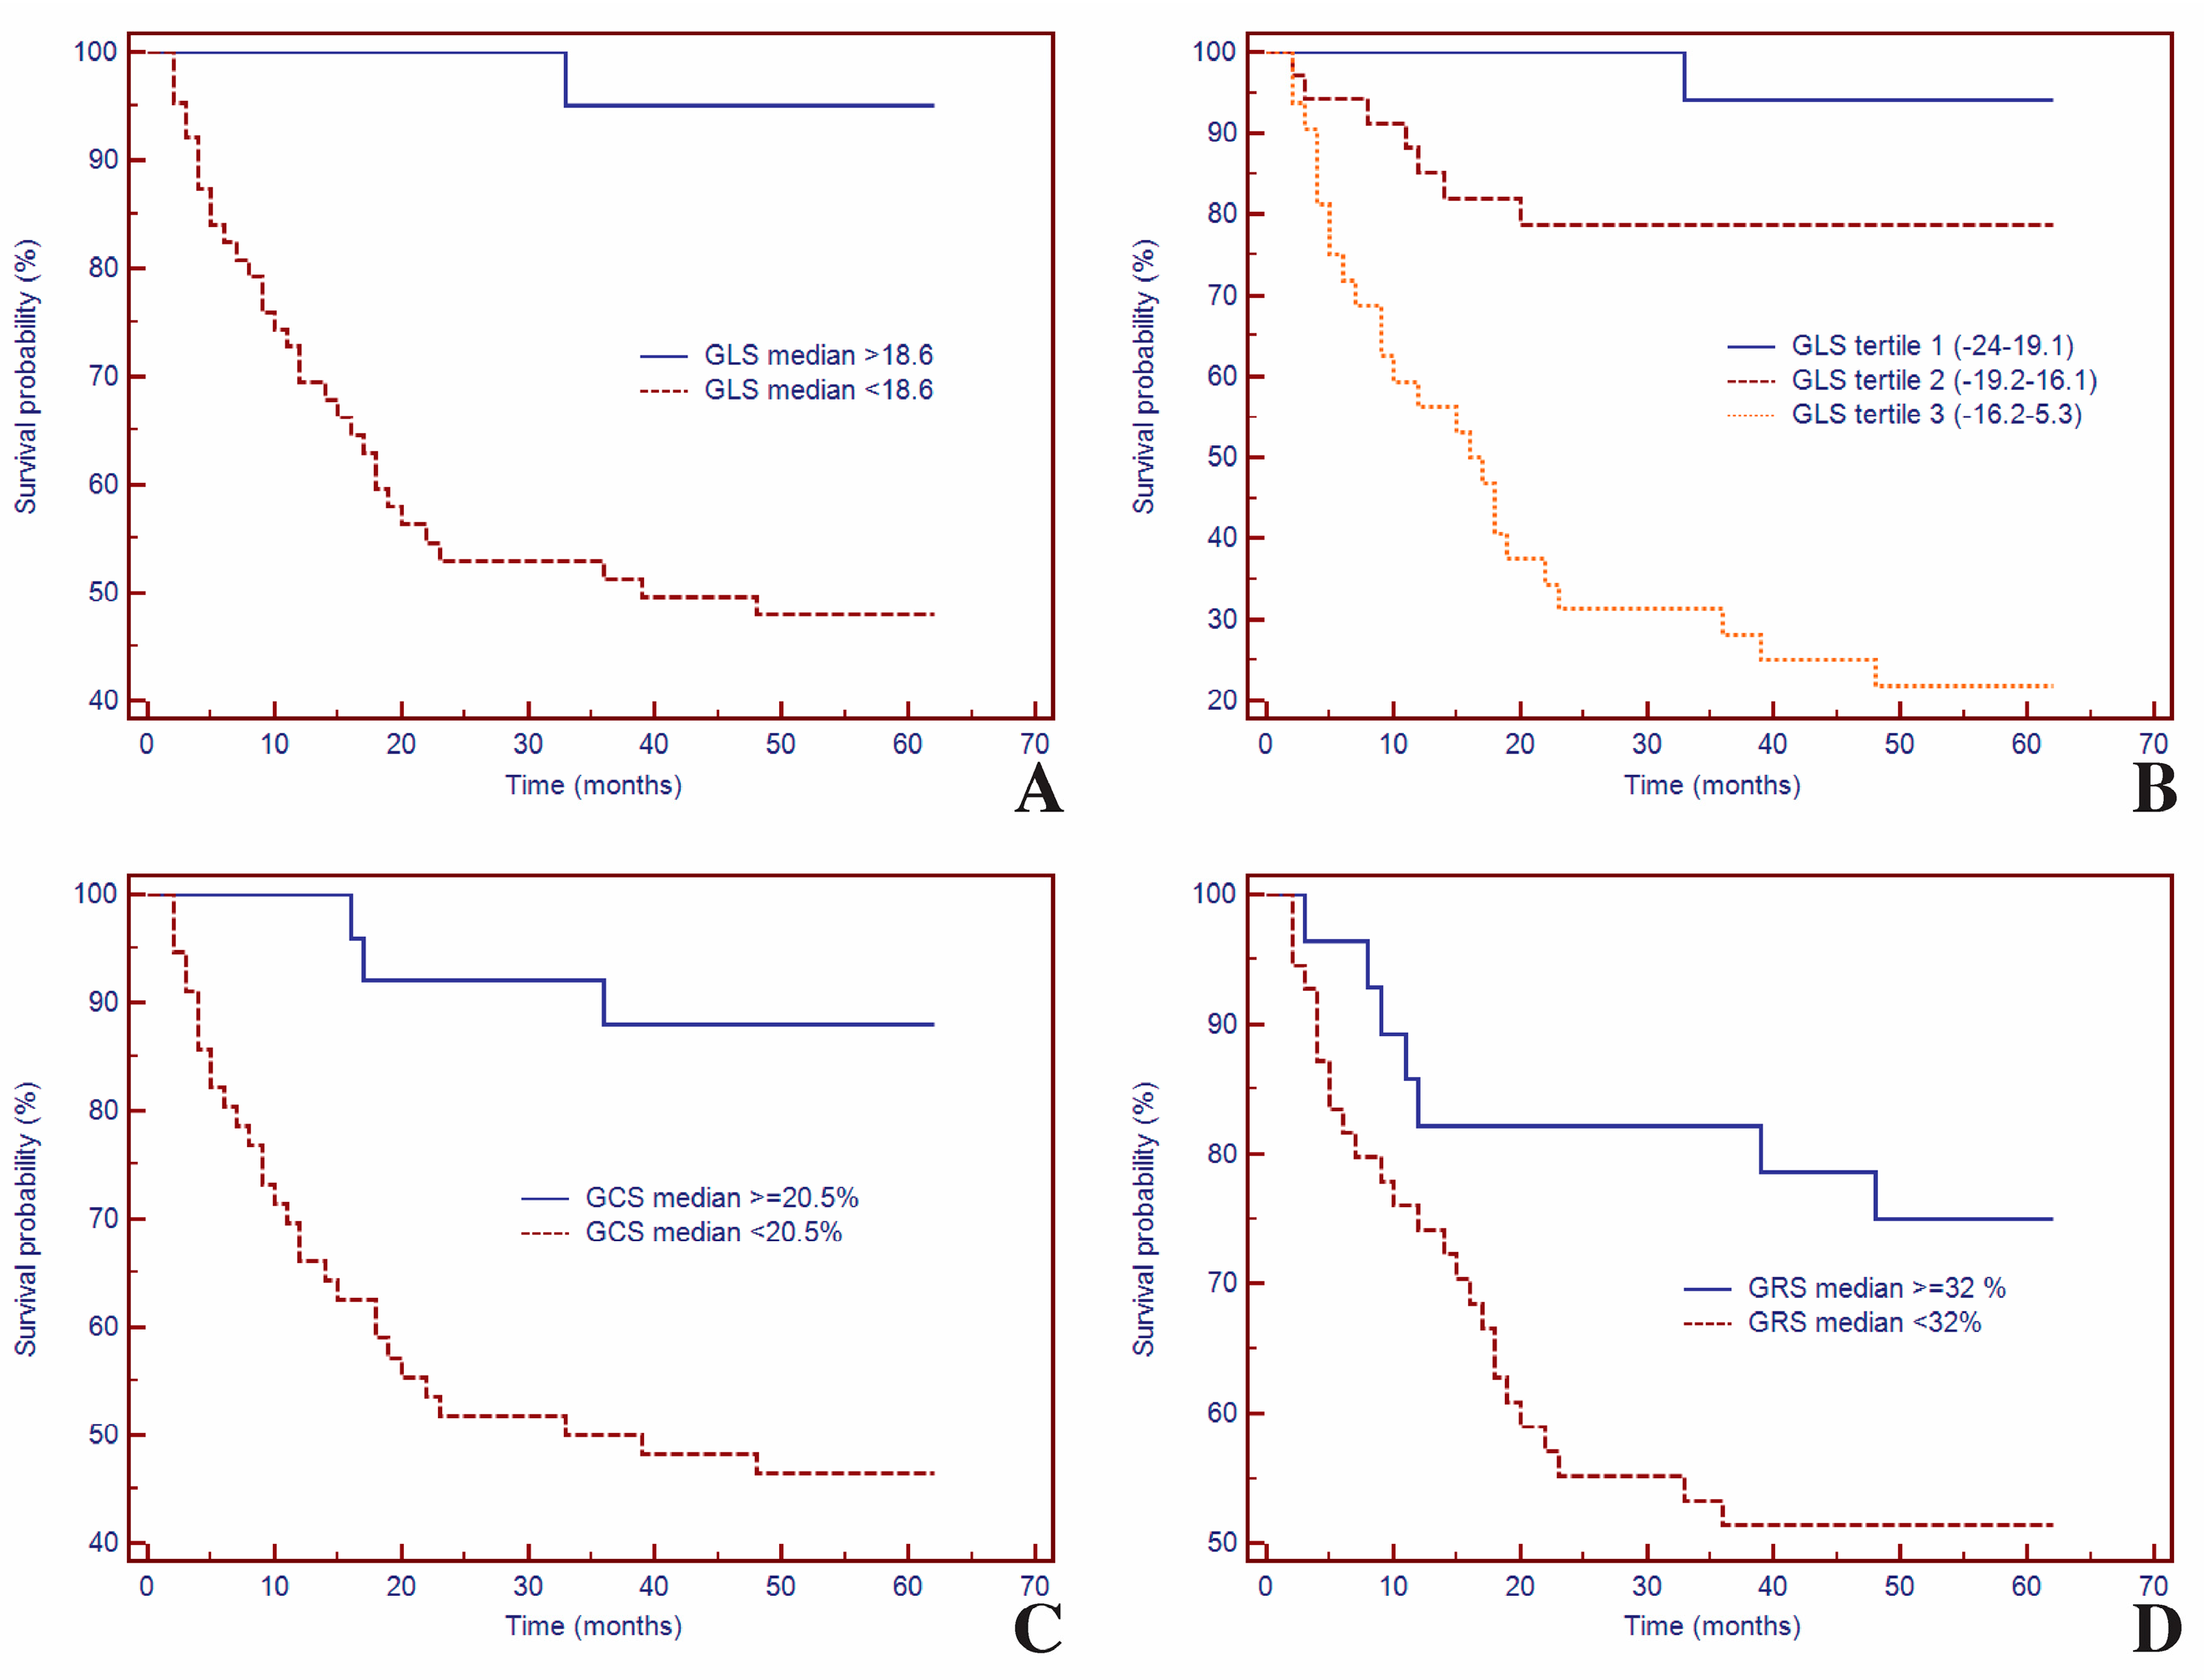

3.5. Survival Analysis of GLS and CMR Parameters for Predicting MACEs

3.6. Univariate and Multivariate Cox Analysis of LV Strain in Predicting MACEs